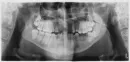

У меня отсутствует 4 передних верхних зуба, еще по одному с каждой стороны молочные зубы. Если их удалить, будет 6 отсутствующих зубов.

В 3-х клиниках мне сказали, что ничем помочь в протезировании не могут, нужна операция остеотомия обеих челюстей. В имплантации отказали, в съемных протезах тоже. Коренные зубы не вылезли с детства, даже снизу ещё имеются молочные зубы.

В первую очередь рекомендуется провести ортодонтическую коррекцию, после чего заняться протезированием с подсадкой костной ткани.